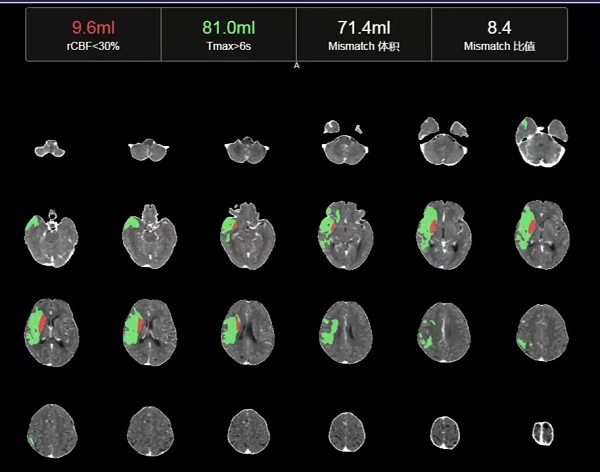

CTP检查结果提示,姬阿姨颅内核心梗死体积约9.6ml(红色区域),但低灌注区域体积高达81ml(绿色区域)(图2),低灌注区域越大,代表可挽救的脑神经细胞越多,手术开通的价值越大,可见患者颅内低灌注区域远远大于核心梗死区域,颅内动脉取栓术手术指征进一步明确。在与患者家属积极沟通,征得家属同意后,王建峰主任团队在国家级高级卒中中心李健主任的指导下,急诊进行了全脑血管造影术+颅内动脉取栓术,术中证实右侧大脑中动脉起始段闭塞(图3),并急诊进行了右侧大脑中动脉取栓术,术中抽拉出一块暗红色血栓,术后可见右侧大脑中动脉血流通畅(图4)。术后1周,在神经内科一病区医护人员的精心照料下,姬阿姨完全康复,说话言语清晰,对答切题流畅,四肢肌力活动恢复正常,现已康复出院。

图3

图4